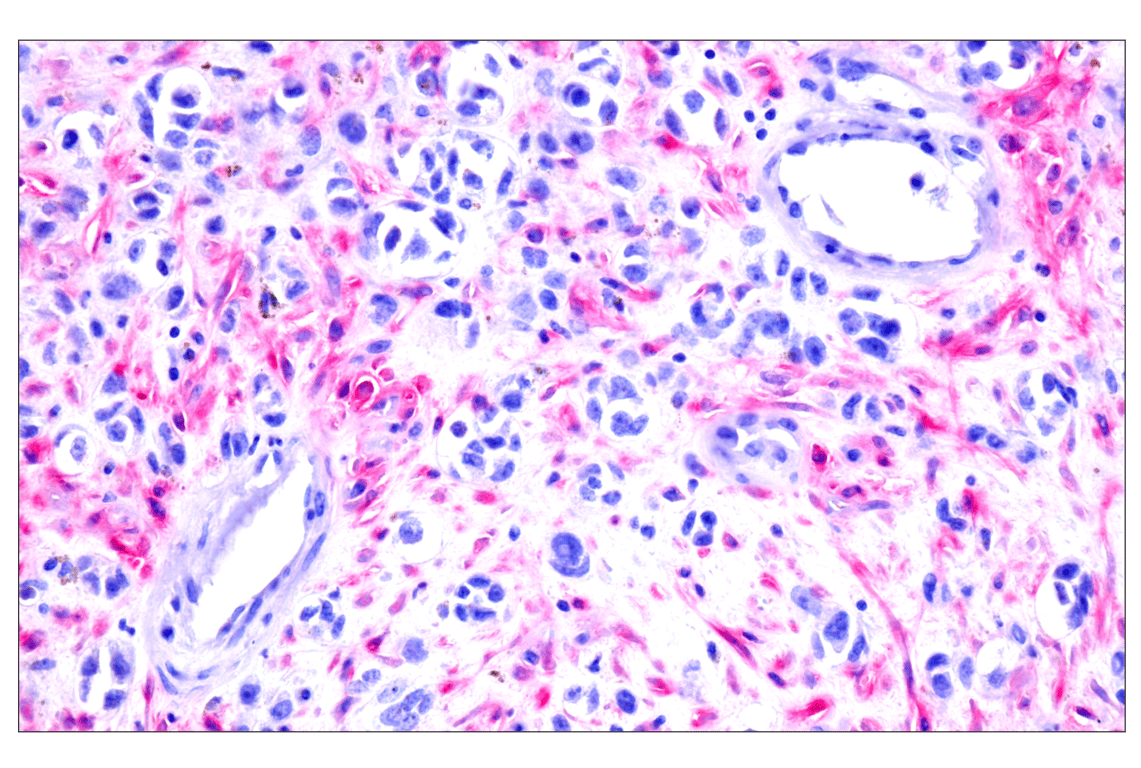

Immunohistochemical analysis of paraffin-embedded human melanoma using FAP (F1A4G) Rabbit mAb. Note the use of the SignalStain® Vibrant Red Alkaline Phosphatase Substrate Kit #76713. Data were generated using the standard formulation of this product.

Immunohistochemistry Image 1: FAP (F1A4G) Rabbit Monoclonal Antibody (BSA and Azide Free)